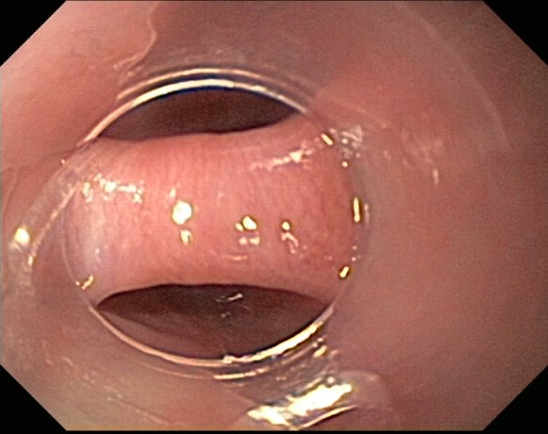

An elderly male presented with dysphagia to solid food, halitosis, and regurgitation. The patient also lost about 10-kg over a 6-month period. Subsequently, the patient underwent an EGD. Note the slit-like entrance to the esophagus. On the next image, a feeding tube is seen in the esophageal lumen. A thin feeding tube is advantageous when endoscopically resecting a Zenker diverticulum for the following reasons:

(a) the tube serves as a reference point to differentiate the esophageal lumen from the diverticulum, (b) It helps guide the incision exactly in the middle of the Zenker's bridge, (c) placing a feeding tube creates a conducible environment for healing and allows for enteral nutrition.